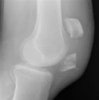

무릎의 AP & lateral X-ray를 시행하며, 수술준비를 해야 하는 경우는 oblique view, CT도 필요할 수 있습니다.

X-ray : 슬개골 골절(Patellar fracture, Broken kneecap)